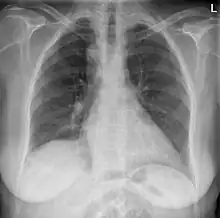

Anterior-posterior chest radiograph showing a right-sided aortic arch |

After birth, a right-sided aortic arch is visualized on chest radiography, by the aortic knob (the prominent shadow of the aortic arch) that is located right from the sternum instead of left. Complex lesions are often assessed by MRI or CT.